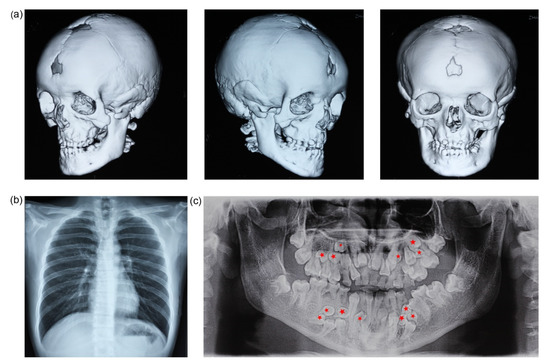

3.1. Clinical Findings